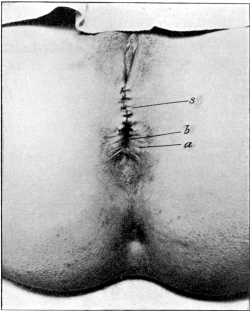

| 30. | Complete Laceration of the Perineum | 127 |

| 32. | Complete Laceration of the Perineum | 128 |

| 33. | Complete Laceration of the Perineum | 129 |